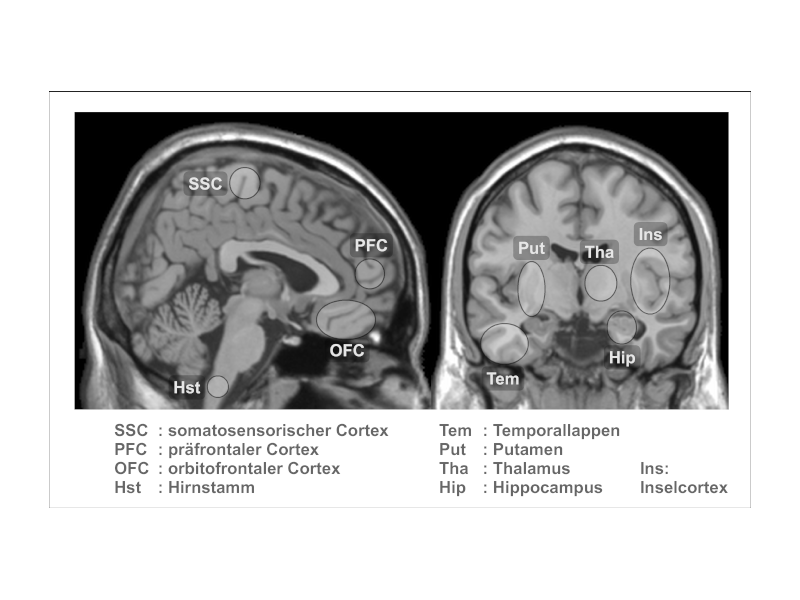

Nach Gründung des Bender Institutes of Neuroimaging durch Prof. Dr. Dieter Vaitl im Jahr 2000 (Vaitl & Ott, 2020) verlagerte sich die Forschungsaktivität auf Techniken zur Induktion von Trance, die keine (Kopf-)Bewegungen beinhalteten, um sie mit funktioneller Magnetresonanztomografie untersuchen zu können (siehe Ott, 2012).

- Im Mittelpunkt standen danach neuronale Korrelate der Meditationspraxis (Gard et al., 2012, Hölzel et al., 2007, 2008, Laneri et al., 2015) sowie potenzielle Risiken von Meditation.